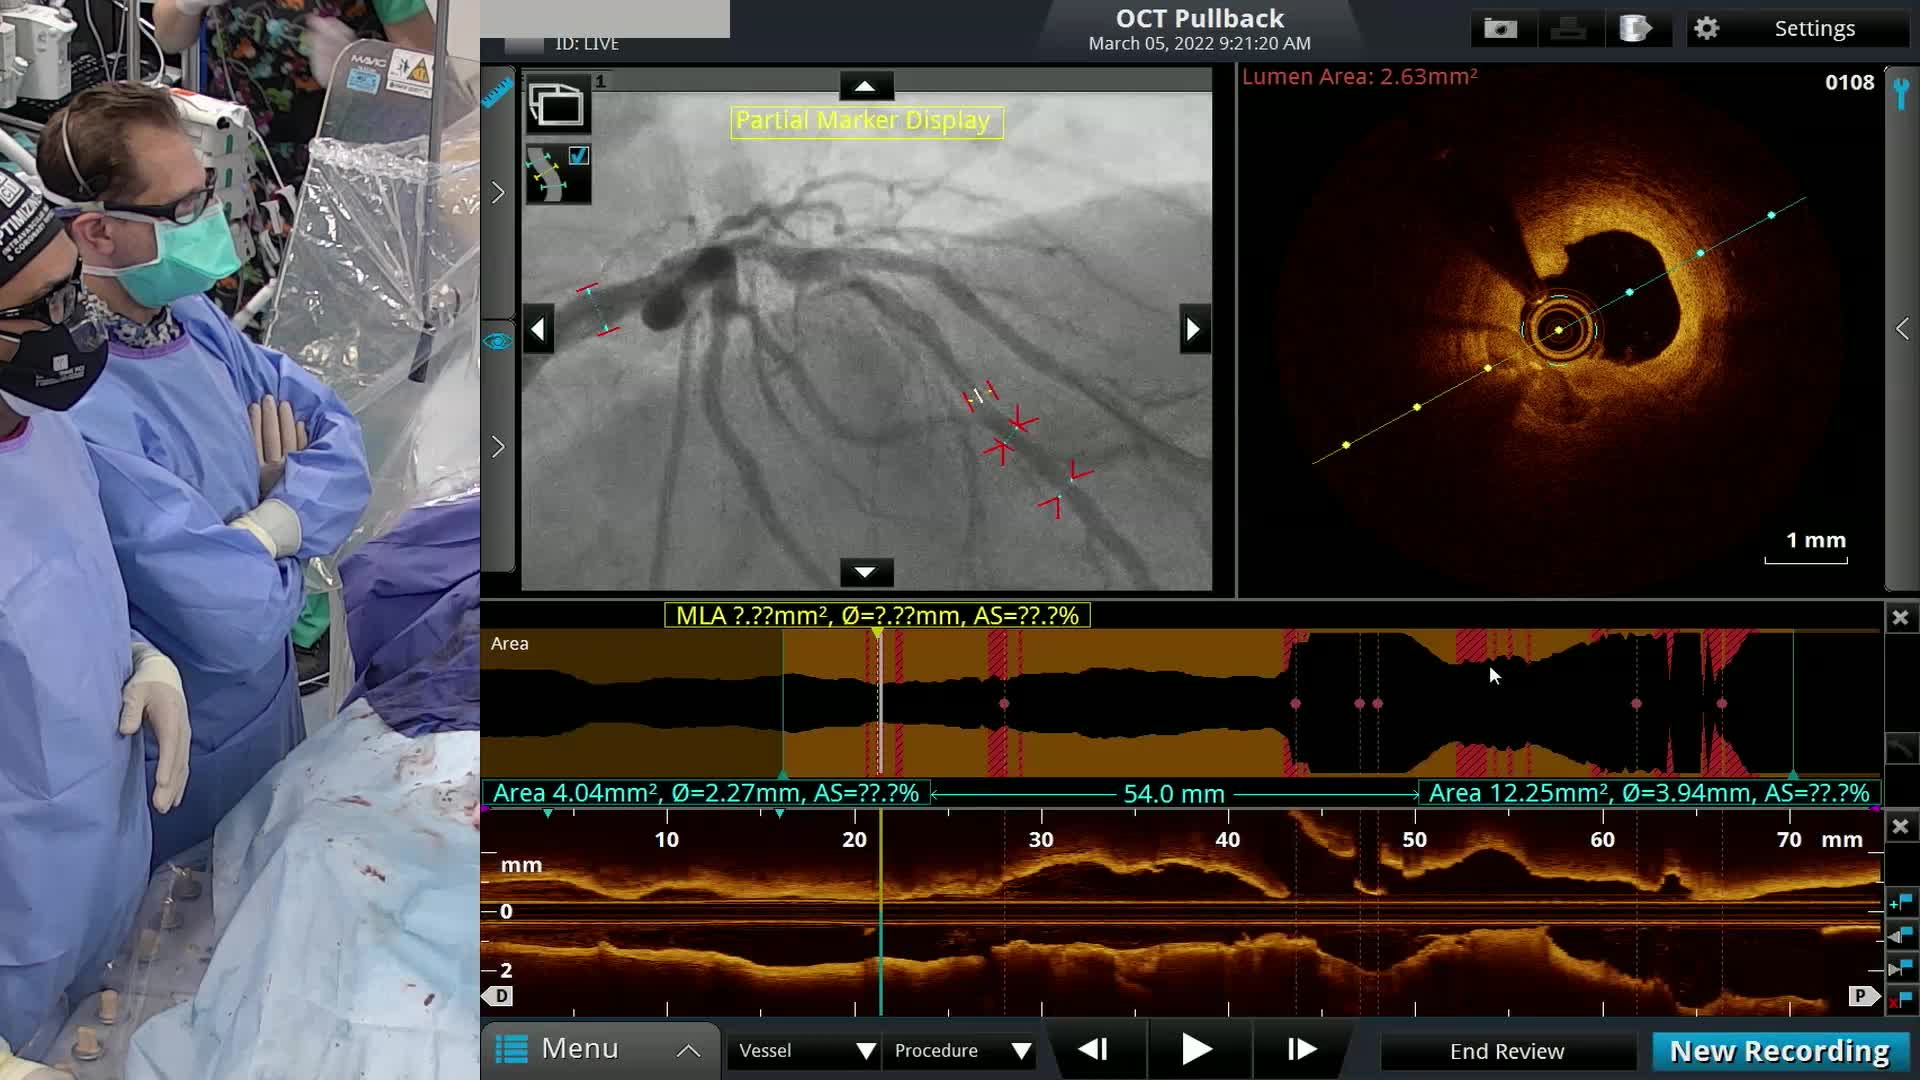

OPCI LIVE - Imaging Guided Treatment of Complex Bifurcation ISR Live Case and Panel Discussion

OPCI

OPCI LIVE - Left Main Bifurcation PCI with Mechanical Support for oLAD-oLCX with Severe In-Stent Restenosis (ISR) Secondary to Underexpansion